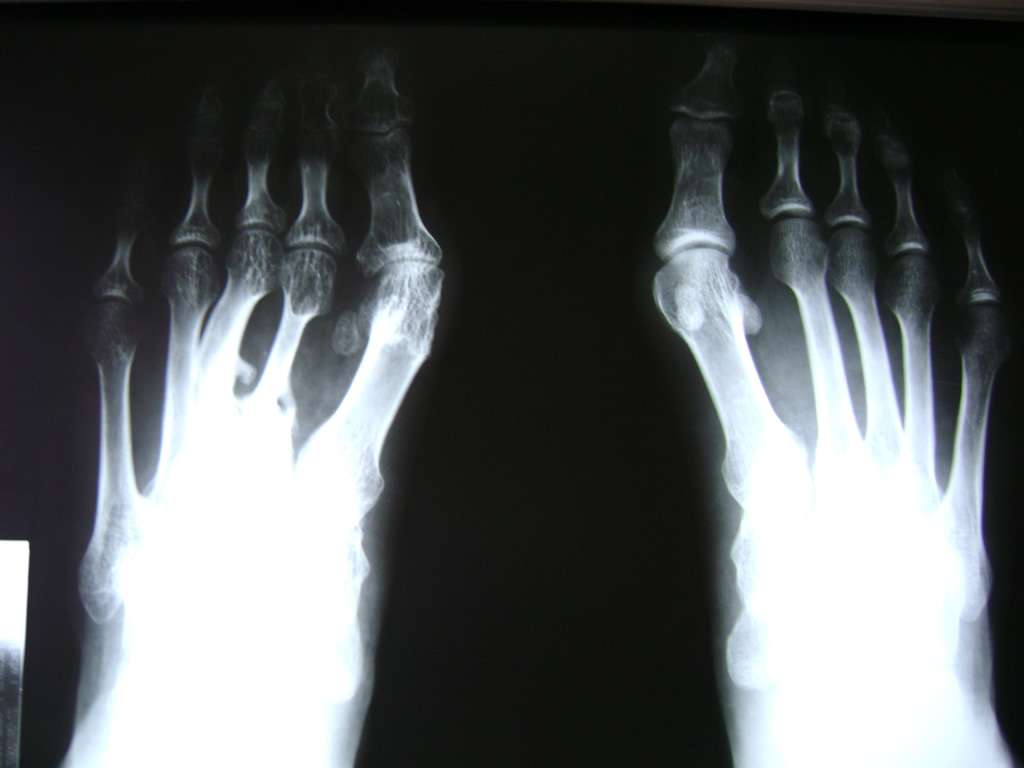

Las deformidades de los pies heredadas o adquiridas son el objeto principal de la cirugía reconstructiva del pie; sobretodo cuando producen dolor con el apoyo debido a una sobrecarga localizada o bien al no ser capaces de adaptarse a un calzado apropiado.

El pie consta de numerosas articulaciones con un mínimo movimiento cuya finalidad es adaptarse al terreno en cualquier situación. Cuando estas articulaciones que soportan grandes cargas y realizan movimientos sutiles se deterioran o funcionan de manera inapropiada, se suelen fusionar con el fin de evitar el dolor o bien restablecer la forma natural del pie y del apoyo.